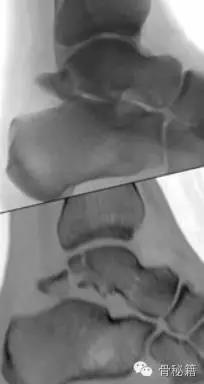

距骨与跟骨接触就有三个关节面如果想要好的功能那么这三个关节面最好都是解剖复位

损伤主要位于以下几个主要部分体、颈、后突、外突